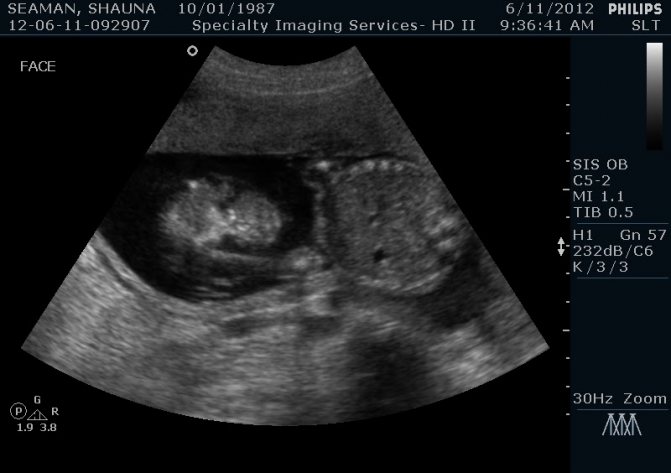

Рис. 2. Лимфосаркома брыжеечного лимфоузла кошки.